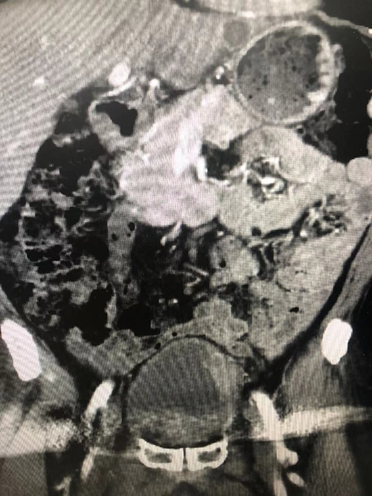

病例五,52岁女性,发现右肾肿物1月。CTU提示右肾癌7.7cm×6.8cm×11.6cm,伴MayoII级下腔静脉癌栓,长6.5cm。既往乙肝肝硬化。贫血。行机器人辅助腹腔镜右肾根治+下腔静脉瘤栓取出术,术者:张洪宪教授。术中发现肿瘤生长迅速,瘤栓较术前3天的影像学检查相比有进展,术中探查发现瘤栓已生长至下腔静脉肝后段,且质地极为糟脆,由于肝后下腔静脉不容易进行近心端阻断,遂采用不阻断近心端方法:充分游离肝后下腔静脉后,术中切开下腔静脉,采用“Milk”技术,用纱布沿下腔静脉近心端将下腔静脉瘤栓向下全部挤压出下腔静脉管腔,之后用纱布压迫下腔静脉近心端做临时阻断,同时缝合下腔静脉壁。